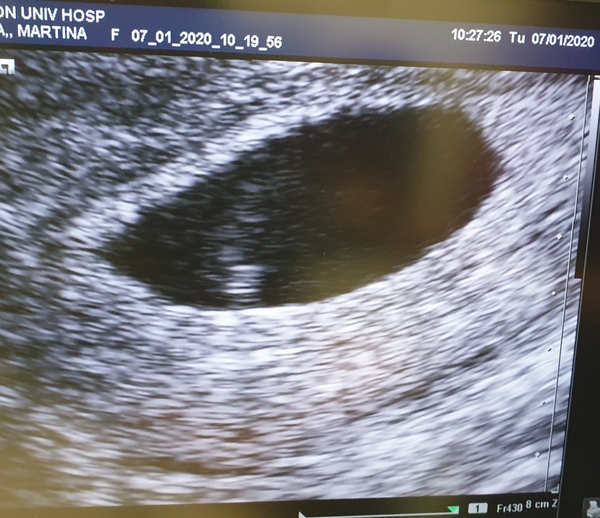

Martina2311 · 07/01/2020 12:57

Hi ladies, went to EPU today for some reassurance because I couldnt wait any longer and received some good news. 6+2 today and a visible heartbeat. I was and still am quite emotional and overwhelmed. I know it's still really early but so happy that everything is as it should be right now. Next scan I am planning is at 8 weeks. Hoping our baby is strong and can hold on tight this time. ❤